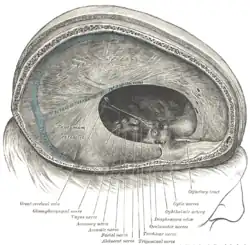

- Es gibt fünf verschiedene Neuroophthalmologische Syndrome: Das Syndrom der Olfaktoriusrinne, des Keilbeinflügels, der Orbitaspitze, das Foster Kennedy-Syndrom und das Sinus-cavernosus-Syndrom.

Hirnnervenfunktion: Es gibt zwölf Hirnnervenpaare. Die Funktion jedes Hirnnerven kann in einer neurologischen Untersuchung geprüft werden. Da dies sehr aufwändig ist, werden Hirnnerven meist nur „orientierend“ untersucht. Das heißt, man macht eine unvollständige Untersuchung unter der Annahme, dass wahrscheinlich alles in Ordnung ist. Wenn jedoch eine Hirnnervenstörung vermutet wird, muss im Zweifelsfall jede einzelne Funktion genau geprüft werden. Die ersten beiden Hirnnerven sind der Nervus olfactorius für den Geruchssinn und der Nervus opticus für den Sehsinn. Das Riechen wird mit Riechstoffen geprüft (z. B. mit Kaffeepulver) und das Gesichtsfeld mittels der sogenannten Fingerperimetrie. Die Hirnnerven III, IV und VI steuern die Bewegungen der Augen (Bewegung eines Fingers des Arztes verfolgen). Der fünfte Hirnnerv ist der Nervus trigeminus. Er versorgt sensibel das Gesicht und motorisch die Kaumuskulatur. Der Nervus facialis ist der siebte Hirnnerv. Er versorgt motorisch die mimische Muskulatur. Der achte Hirnnerv ist für Gehör- und Gleichgewichtsorgan zuständig. Hier kommt der Stimmgabeltest zur Anwendung. Den Gleichgewichtssinn prüft man sinnvollerweise nur, wenn er gestört ist. Die Patienten haben dann ein Schwindelgefühl. Zu diesem Zweck gibt es spezielle Methoden, mit denen man Schwindel provozieren kann. Der neunte Hirnnerv ist der Nervus glossopharyngeus. Er hilft beim Schlucken und vermittelt auch den Geschmack im hinteren Zungendrittel (dort schmeckt man bitter). Der zehnte Hirnnerv ist der Nervus vagus, er vermittelt die vegetative parasympathische Innervation der inneren Organe. Er versorgt sensorisch außerdem die Ohrmuschel und motorisch das Gaumensegel. Der elfte Hirnnerv steuert einen Teil der Nackenmuskulatur und der zwölfte Hirnnerv (Nervus hypoglossus) bewegt die Zunge.